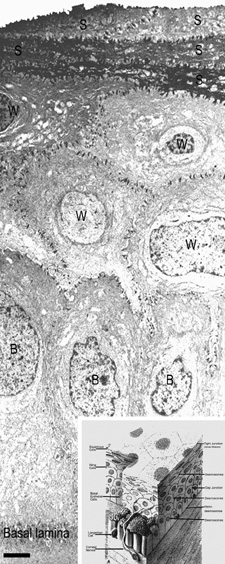

The anterior surface of the human cornea is covered by a transparent, nonkeratinized, stratified (five- to seven-cell layer) squamous epithelium uniformly around 50 μm in thickness that is continuous with the epithelium of the limbus and conjunctiva (Figs. 1, 2, and 3). The basal corneal epithelial cells actively secrete extracellular material (type IV collagen, laminin, heparin, and small amounts of fibronectin and fibrin) that forms an underlying 75-nm thick basement membrane called the basal lamina. On electron microscopy, the morphology of basal lamina appears to be composed of two distinct layers: a 25-nm thick lamina lucida and a 50 nm thick lamina densa (Fig. 3).

Fig. 3. Transmission electron micrograph (3,500×) of the central corneal epithelium with a summary diagram (inset). Microvilli project from the anterior corneal surface into the tear film. S, squamous cells; W, wing cells; B, basal epithelial cells. Bar = 1 μm. (Inset modified from Hogan MJ, et al. Histology of the human eye. Philadelphia, WB Saunders, 1971.)

The epithelial cells differentiate from the basal layer to form two to three cell layers of wing cells and finally to form two to three cell layers of squamous cells (Fig. 3). The squamous cells form a barrier junction because they are surrounded by a continuous encircling band of zonula occludens tight junctions, which serve as a semipermeable, high-resistance (12–16 kΩ cm2) membrane6,7 by closing off the intercellular space. This barrier prevents the movement of fluid from the tears into the stroma and also protects the cornea and intraocular structures from infectious pathogens. The apical surface of the corneal epithelium is specialized to maintain the tear film as microplicae and microvilli on the surface of the most superficial epithelial cells is covered with a glycocalyx and membrane-spanning mucins (MUC 1 and possibly MUC 4); altogether these structures and substances form the 1.0 μm thick mucinous layer of the tear film (Fig. 5).8–10